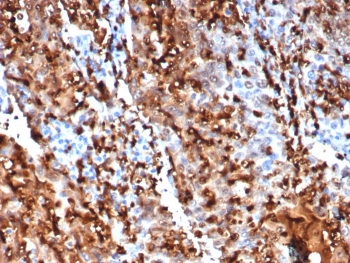

Cathepsin D Antibody

| Description | Cathepsin D Antibody |

| Tested applications | FC, ICC, IHC, IP, WB |

| Reactivity | Human, Mouse |